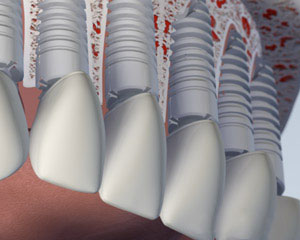

另一种选择涉及将四到六种植体, 这取决于你的下巴大小或形状, 进入你的下颚. 后完全愈合, 植入物与一个特制的支撑杆连接. 你的假牙将与附着到支撑条特殊的内部固定夹进行, 使假牙牢固卡入到位. 这就是所谓的 “覆盖义齿.” 这个方案的优点是,它更稳定比第一个选项,允许非常小的义齿运动. 你的义齿仍然是可拆卸,便于清洁和维护.

第三种选择包括将五个或更多的植入物在你的下巴和安装永久假牙. 假牙代替由它固定在支撑柱或棒螺钉或扣环举行. 它不接触牙龈组织, 它可以让你的假牙清洁下而不删除它. 这假牙将替换所有丢失的下齿,除了在维护访问将不会被删除. 虽然清洁假牙下,而不移除它耗费更多的时间和需要更多的灵活性, 谁想要一个永久性的义齿很多患者喜欢这个选项.

最后一个选项是让所有你的牙齿单独更换,使他们看起来是生长出来的牙龈组织,将最相似的天然牙的外观. 此选项通常需要八个或更多 植入物. 单独的基牙或这些植入物中的每一个支撑柱将被制成,每个缺齿冠将被放置. 牙齿往往是结合在一起的 窦嫁接 更换骨高度实力作支撑. 总体, 这是最昂贵的选择, 因为它需要最植入物和个体替代牙制作. 您所更换的选项也可以通过您的颌骨的电流大小和形状的限制.

3. 修复完成

如果你想恢复类似于你的自然牙齿,因此不可拆卸, 您可能需要八到十个人 植入物放置. 这是由基台和新更换的冠的位置愈合后跟随.